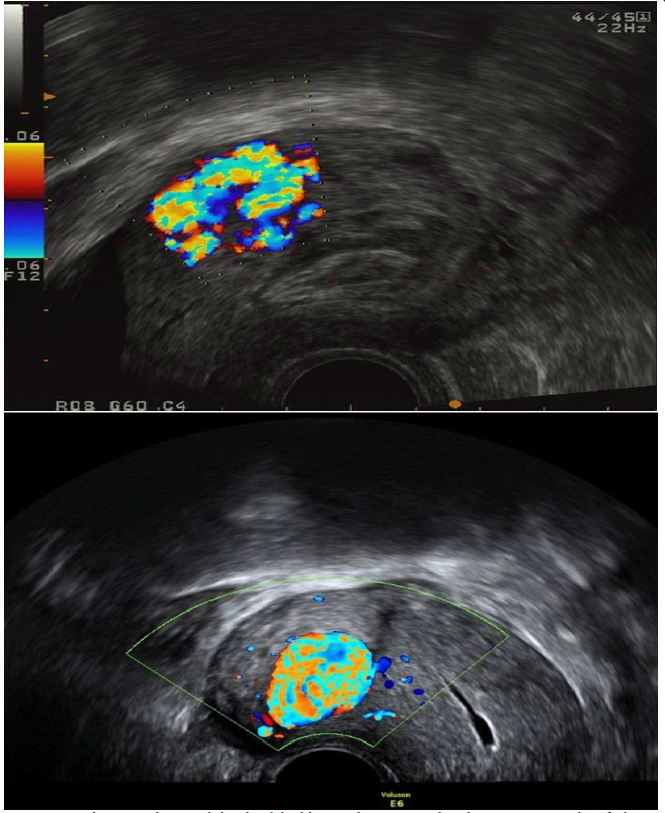

Figure 14: Colour Doppler reveals localised, highly vascular AVMs within the myometrium identified on transvaginal scan (sagittal plane).

figure 14